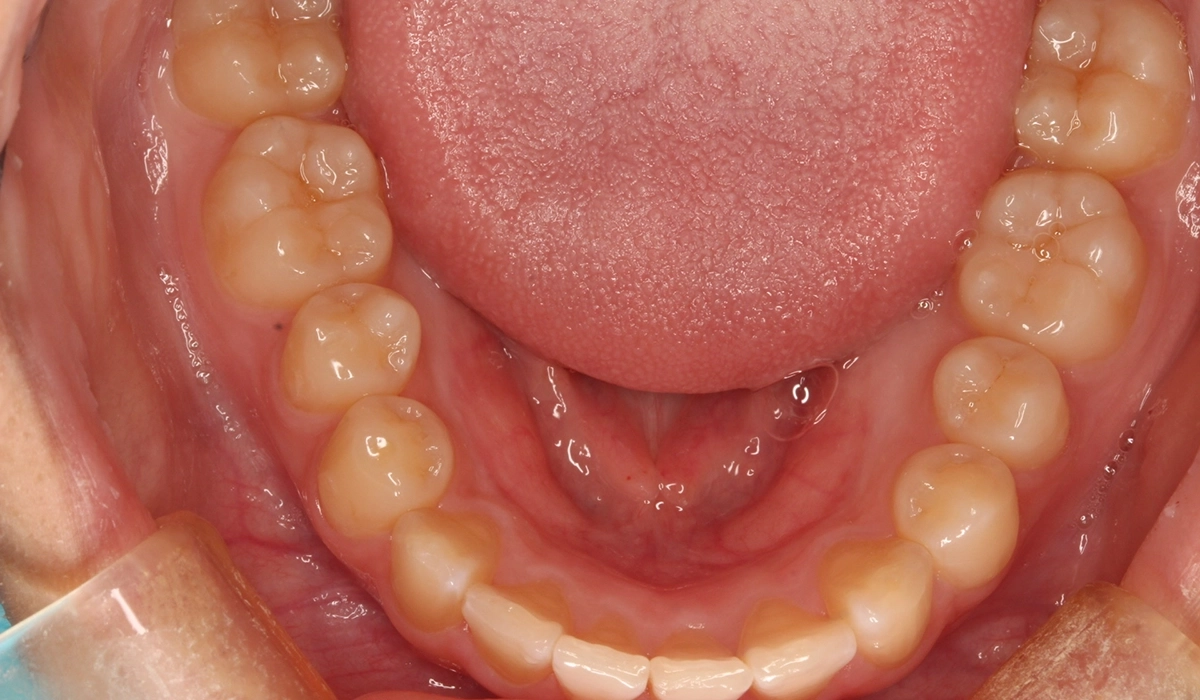

術前:下顎

術後:下顎